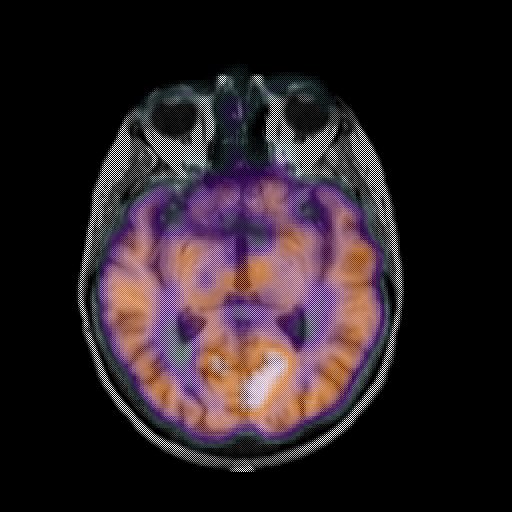

overlay: Slice 25

Slice 25

MRCBFCBF with

T1PDT2T1PDT2